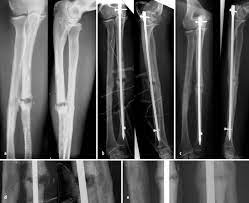

Bei den dabei verwendeten sogenannten Marknägeln handelt es sich meist um Implantate aus Titan oder Edelstahl. Die Diagnose Multiples Myelom in Deutschland fälschlicherweise oft mit dem solitären Plasmozytom gleichgesetzt löst Schock Angst und Ratlosigkeit aus. Es blieben subtrochantär große Löcher im Femur mit einer lateralen kortikalen Lücke von 12x12 mm und einer weiteren.

Immerhin wird das Bein bin zum Knochen geöffnet Gewebe und Muskeln durchtrennt und es verbleiben Löcher in den Knochen. Die Schraube im Schenkelhals ließ sich noch lösen die zwei Verriegelungsschrauben jedoch nicht - die Schraubenköpfe brachen ab die Gewinde wurden überbohrt und brachen wieder ab. Da die Drähte bei auch nur leichter Lockerung eine Gefahr für Strecksehen darstellen gibt es sehr gute Gründe die Kirschnerdrähte zu entfernen.

Es wurde schließlich alles Metall entfernt aber leider zu einem hohen Preis.

Gelegentlich ist es nicht möglich das Material vollständig zu entfernen so dass es auch vorkommen kann dass Reste des Metalls im Körper belassen werden müssen. Ich habe neulich das Gleiche bei einem Schrank erlebt. Die Stabilität sollte nach der Entfernung kein Problem sein weil die Schrauben und Nägel immer versetzt angeordet sind also die Löcher nie über- untereinander lägen. Die ist hart und sehr spitz und lässt sich nicht bewegen. Sollten Metallteile weggebrochen sein werden die dann auch im Knochen belassen die tun nix. Hier ist die Radiusfraktur nicht mit einer Platte sondern mit Kirschnerdrähten erfolgt. Obwohl ein Schraubenloch noch lange im Röntgenbild nachweisbar ist kommt es zu einer fortschreitenden Geflechtknochenbildung die die Stresskonzentration im Schraubenloch zunehmend herabsetzt. Hierbei wird in manchen Fällen lediglich die einzelne Stellschraube entfernt wobei die komplette Metallentfernung ungefähr nach einem Jahr beginnt. Auch nach einem Jahr kann man im Röntgenbild nach einer Schraubenentfernung die Schraubenkanäle gut erkennen.